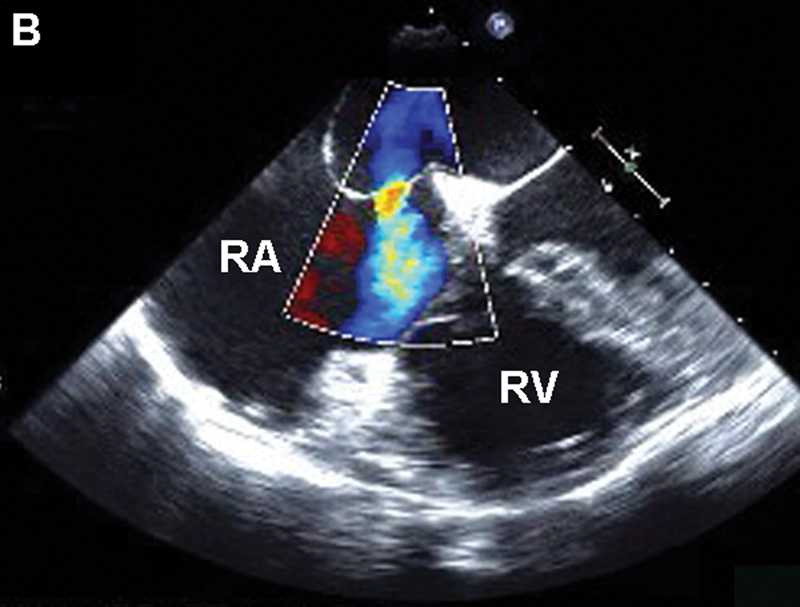

فحوصات تشخيصية لبعض امراض القلب والشرايين التاجية